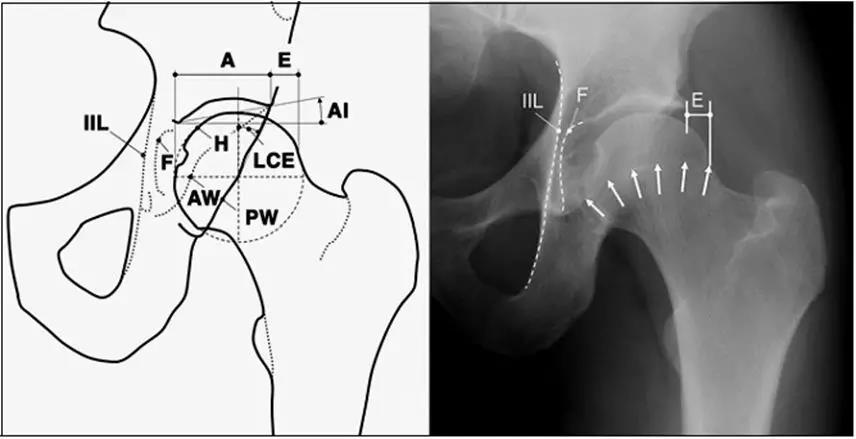

- 中心边缘角(LCE角)正常范围为25一39;髋臼指数(AI)正常值>0;挤压指数(E/A+E)正常值<25%。

- IIL:髂坐线;AW:髋臼前壁缘;PW:髋臼后壁缘;A为股骨头被髋臼覆盖部分的宽度;E为股骨头未被髋臼覆盖部分的宽度;F为髋臼窝线。

髋臼过深,髋臼窝线位于髂坐线内侧。

- 髋臼窝线位于髂坐线内侧。

- LCE>39°时,提示髋臼过渡覆盖。

- 正常髋臼指数(AI)为正值,AI为0或负值提示髋臼过深。

- 髋臼过深:髋臼线位于髂坐线内侧。

- 髋臼突出:更内侧(成人:男性>3mm,女性>6mm;儿童:男性>1mm,女性>3mm。)

- 髋臼前突,股骨头与髂坐线相交